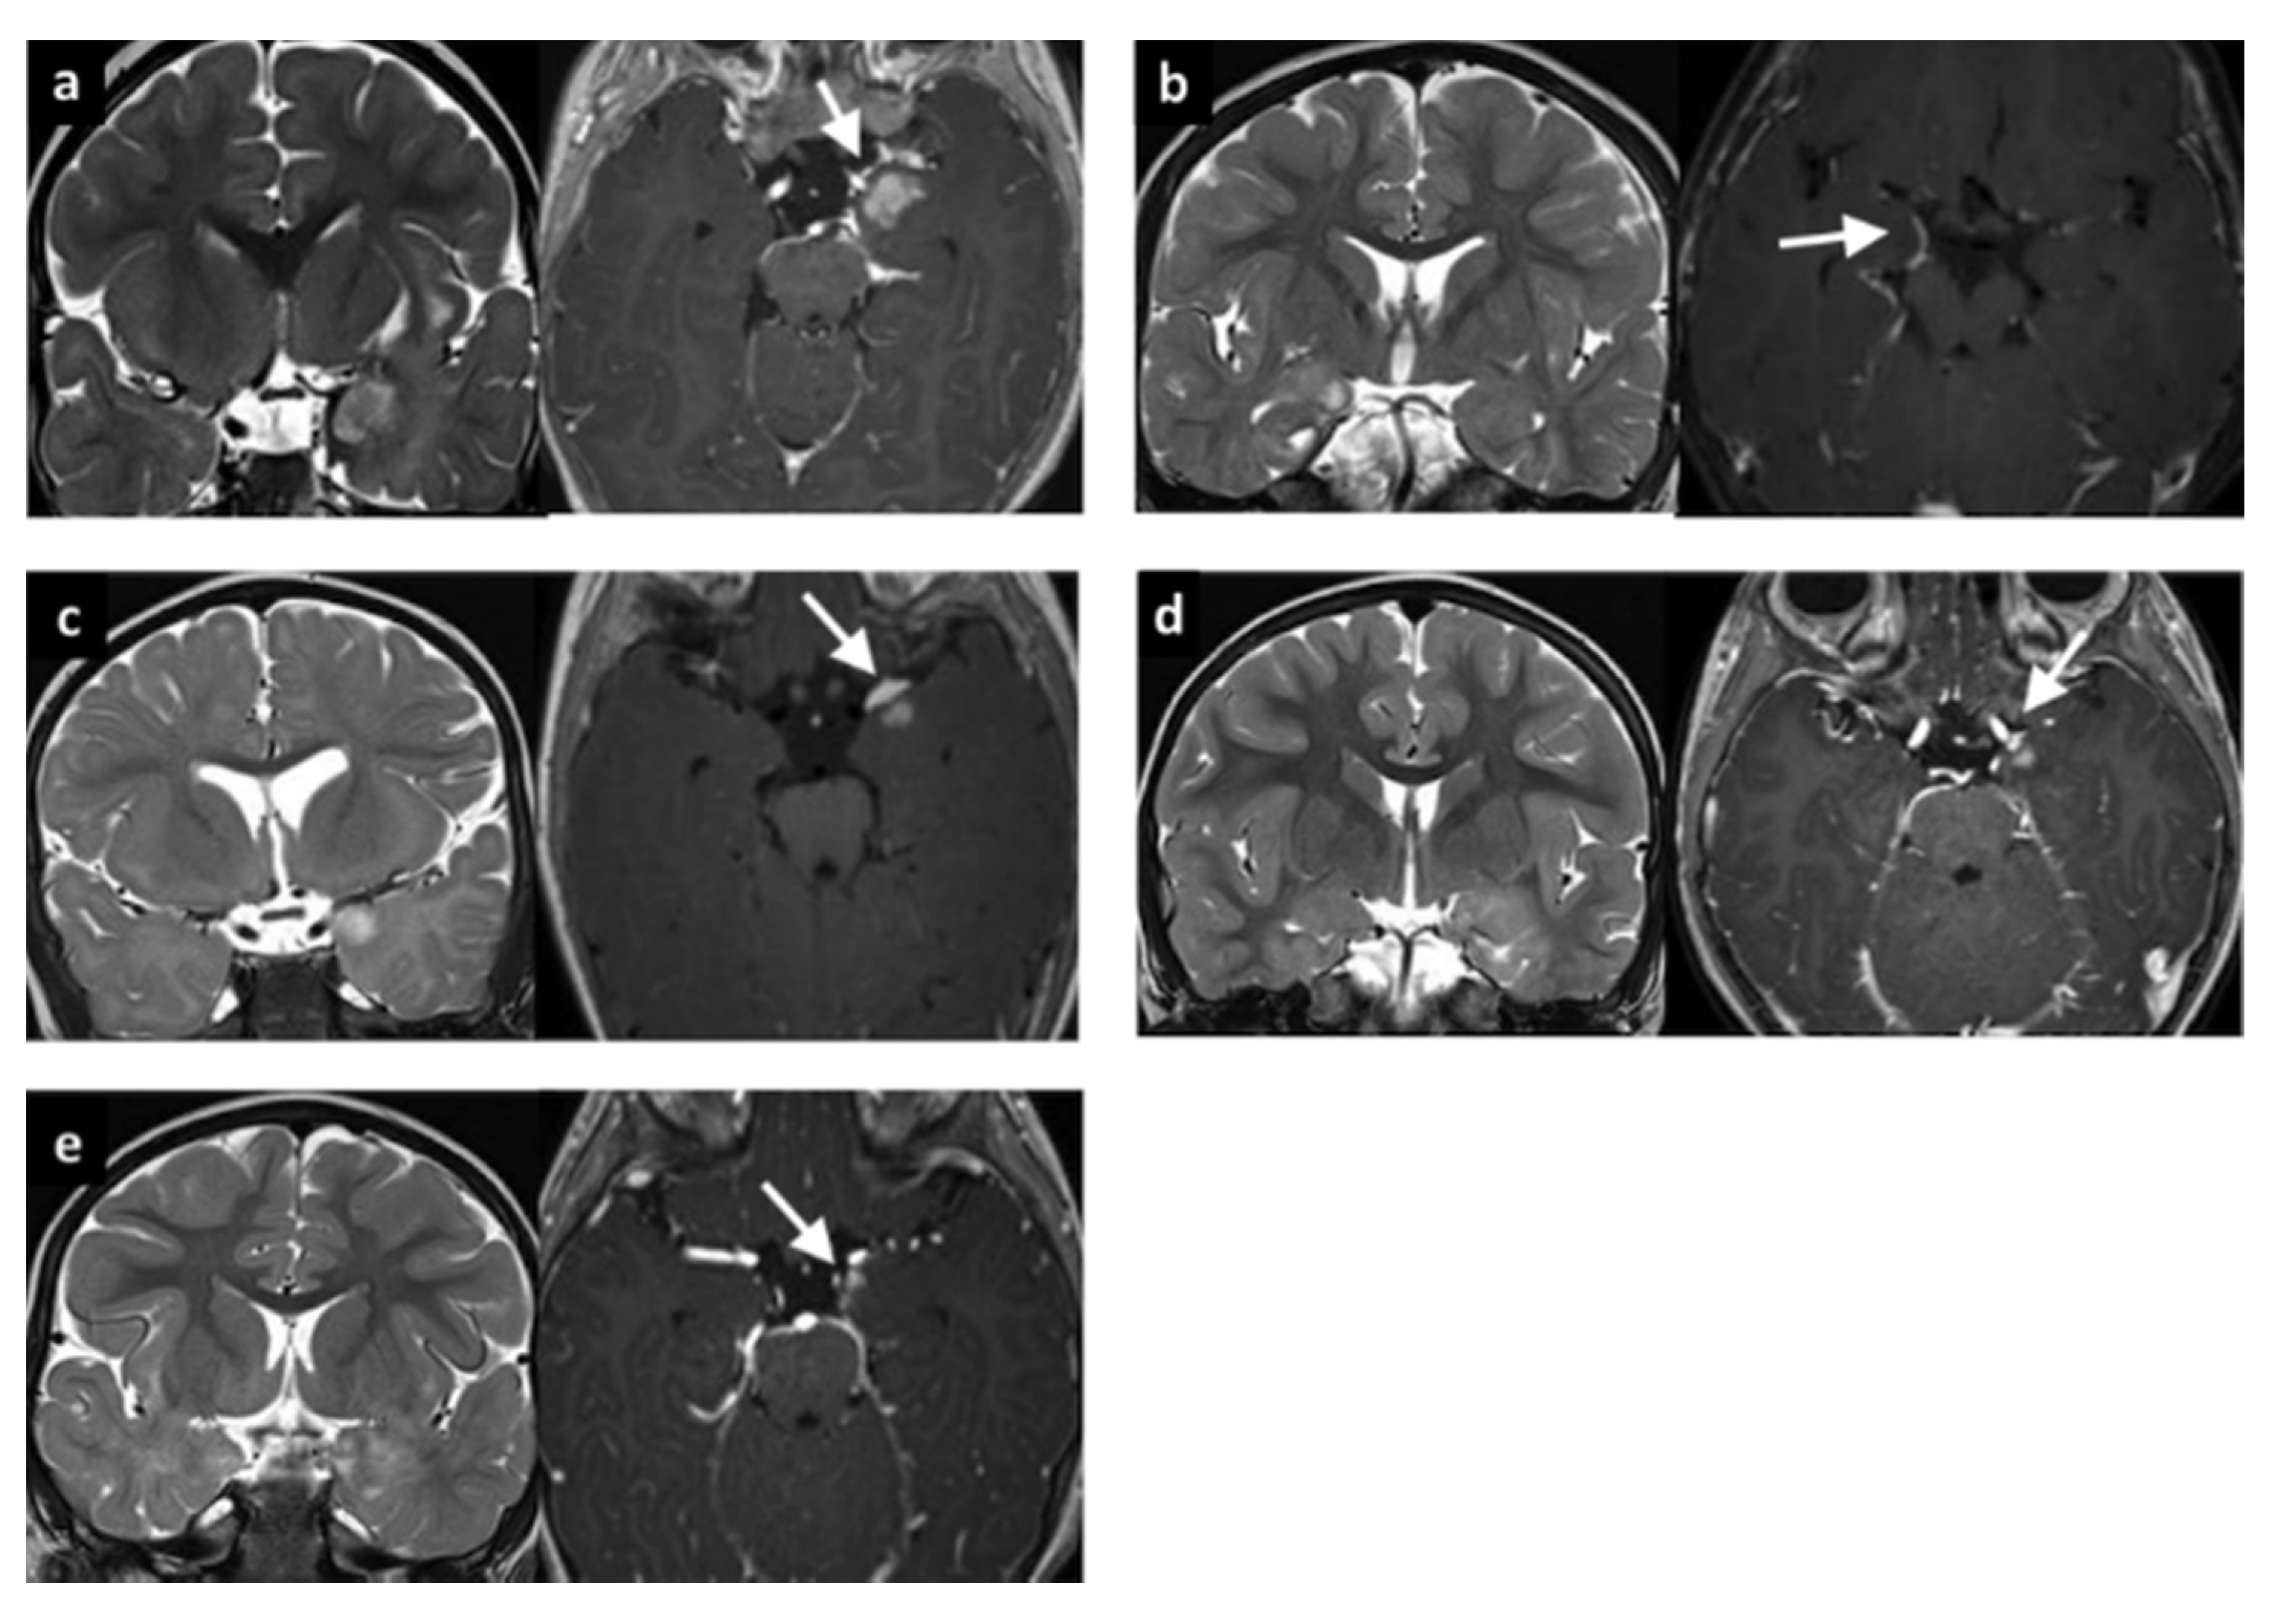

3.1. LEATs with MI (Group 1)